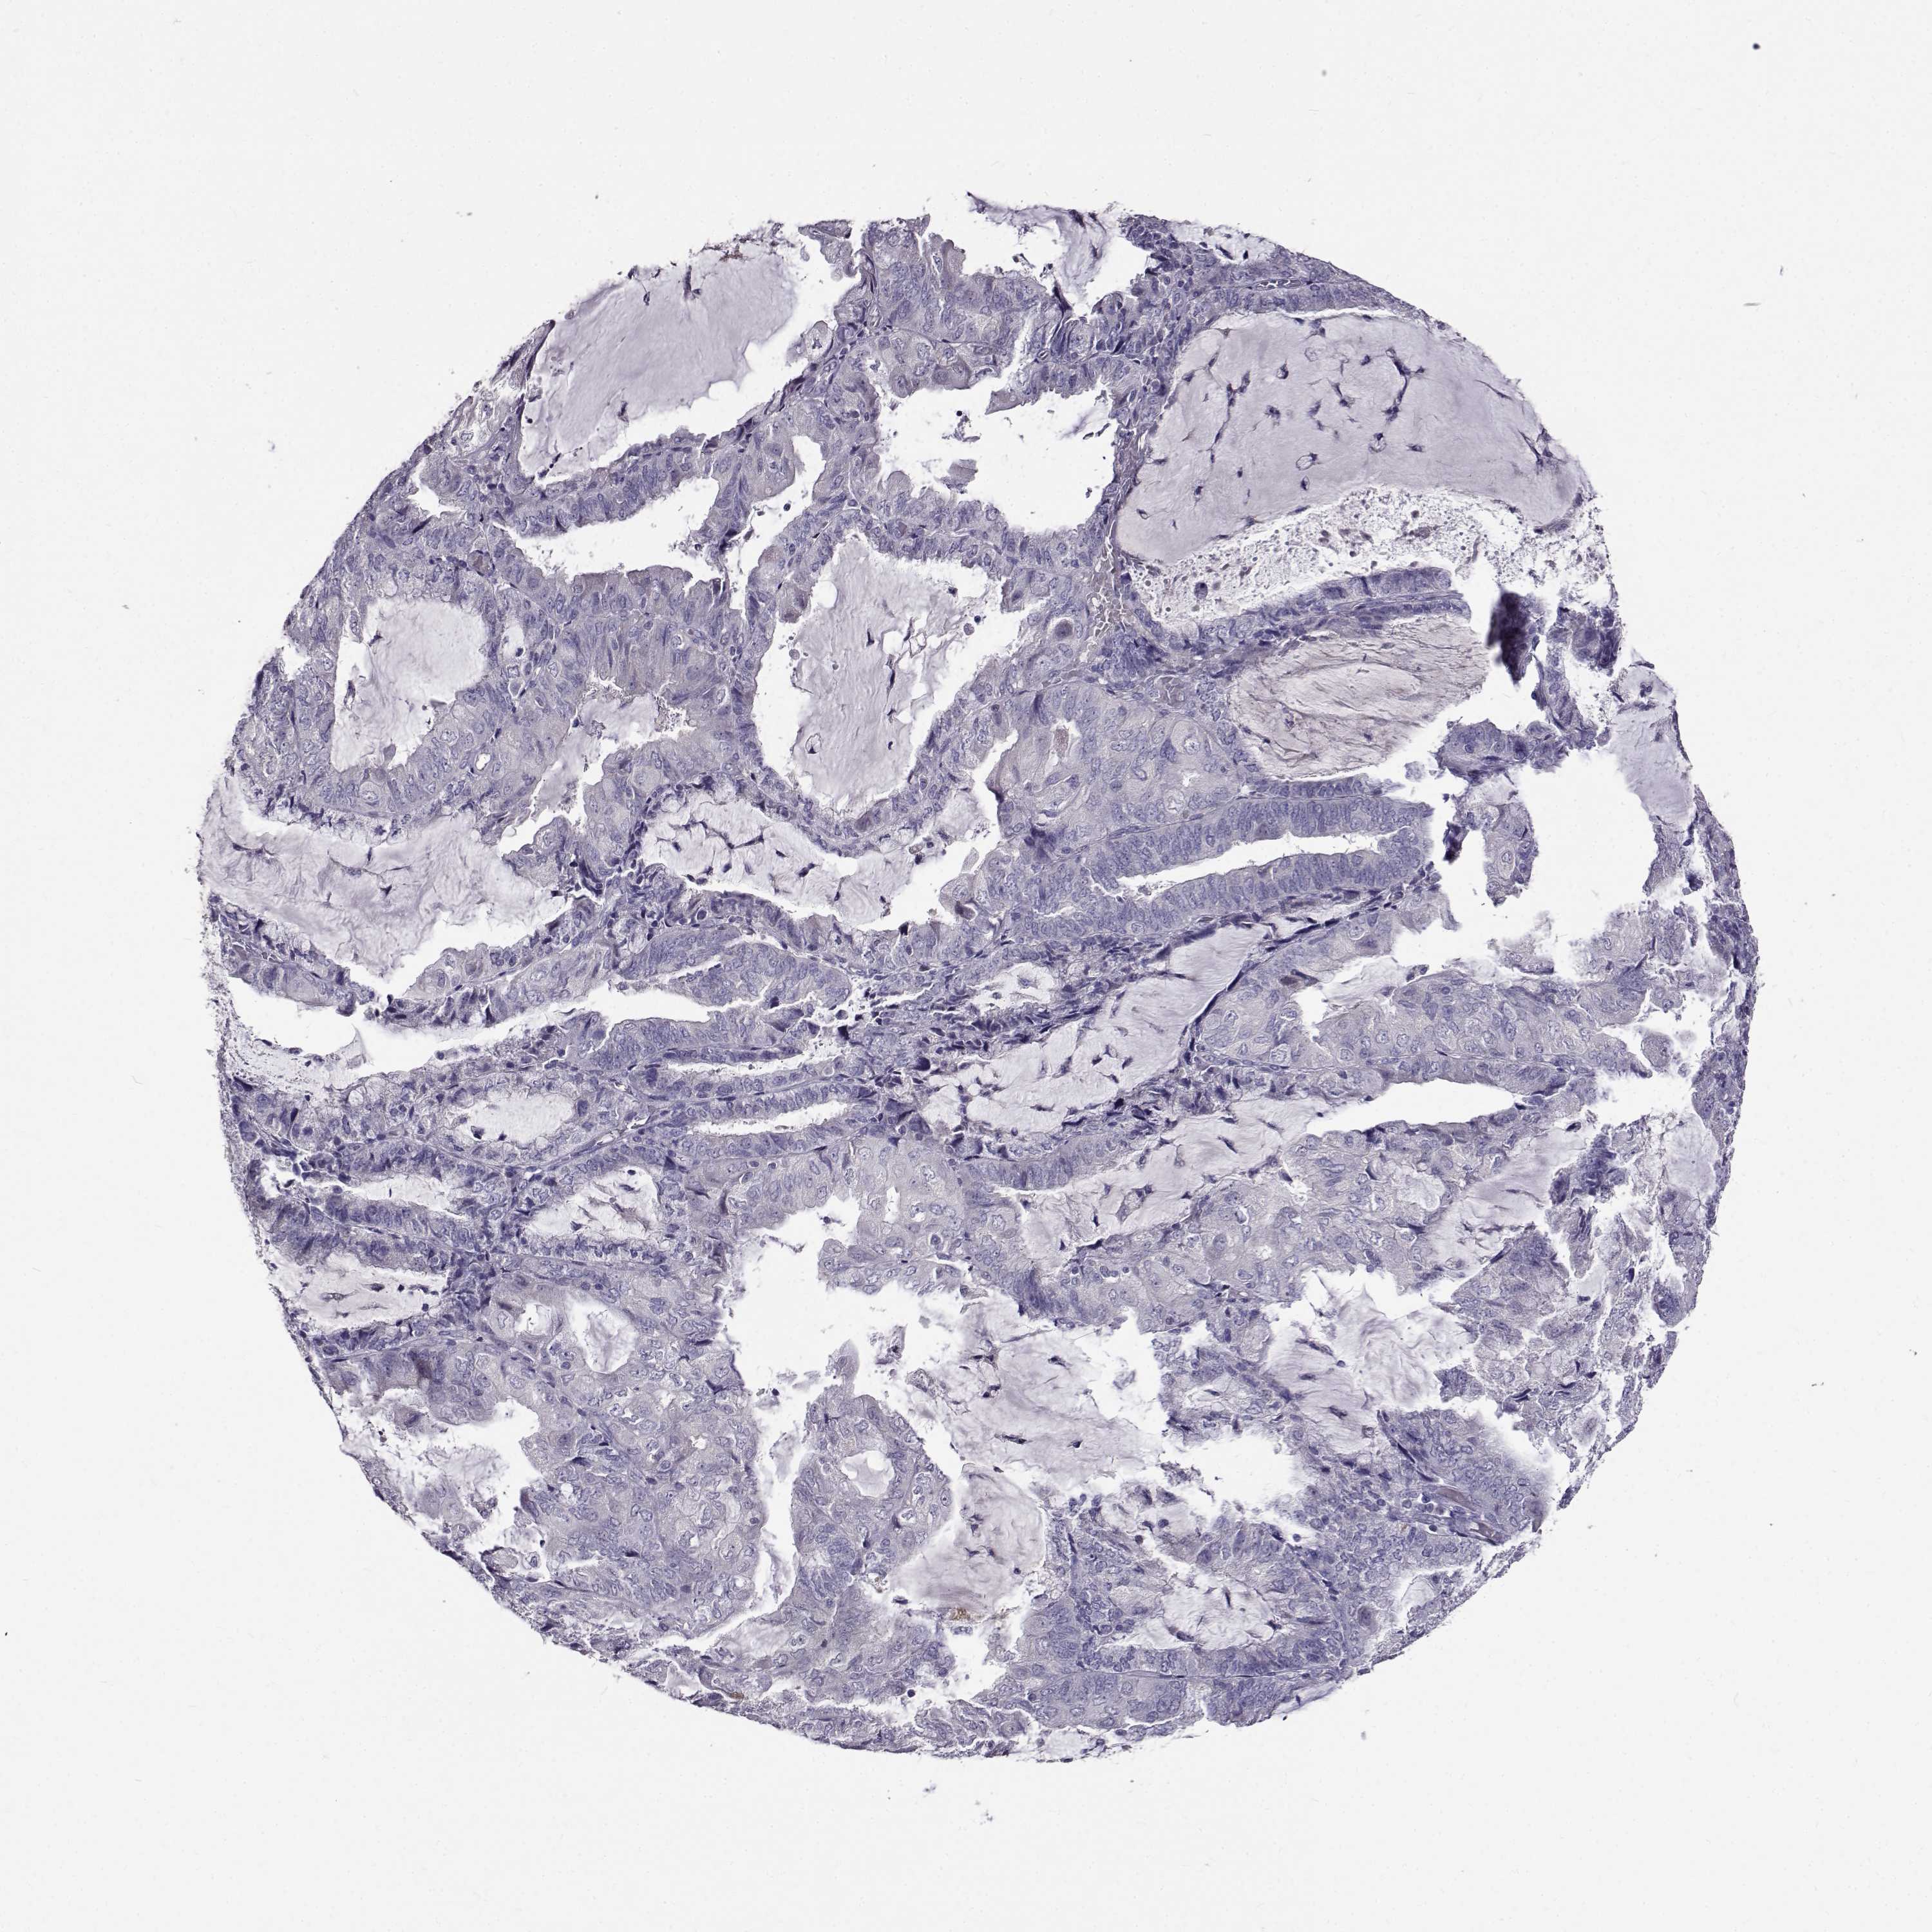

ENDOMETRIAL CANCER - Protein expressioni

A mouse-over function shows sample information and annotation data. Click on an image to view it in a full screen mode. Samples can be filtered based on level of antibody staining by selecting one or several of the following categories: high, medium, low and not detected. The assay and annotation is described here.

Note that samples used for immunohistochemistry by the Human Protein Atlas do not correspond to samples in the TCGA dataset.

Antibody stainingi

Antibody staining in the annotated cell types in the current human tissue is reported as not detected, low, medium, or high, based on conventional immunohistochemistry profiling in selected tissues. This score is based on the combination of the staining intensity and fraction of stained cells.

Each image is clickable and will lead to virtual microscopy that enables deeper exploration of all samples and also displays staining intensity scores, fraction scores and subcellular localization as well as patient and tissue information for each sample.

Antibody HPA020108

Antibody HPA029473

Antibody CAB016762

Staining

High

Medium

Low

Not detected

Intensity

Strong

Moderate

Weak

Negative

Quantity

>75%

75%-25%

<25%

None

Location

Nuclear

Cytoplasmic/membranous

Cytoplasmic/membranous,nuclear

Adenocarcinoma, NOS

Adenocarcinoma, metastatic, NOS

Carcinoma, NOS